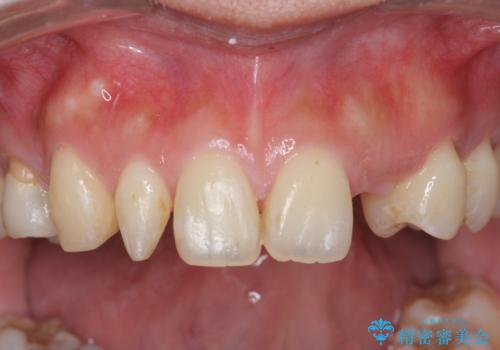

前歯の審美的なブリッジ (歯列矯正後)

- 歯列矯正後に前歯にブリッジを入れた方の経過です。

矯正治療で歯の位置を整えてからブリッジを入れると歯の幅を自由に設定できるため、左右対称にできます。結果矯正なしでいきなりセラミックにする場合と異なり、無理に角度を変えたりする必要がなく、神経をなるべく温存したまま審美的なセラミック治療が行えます。